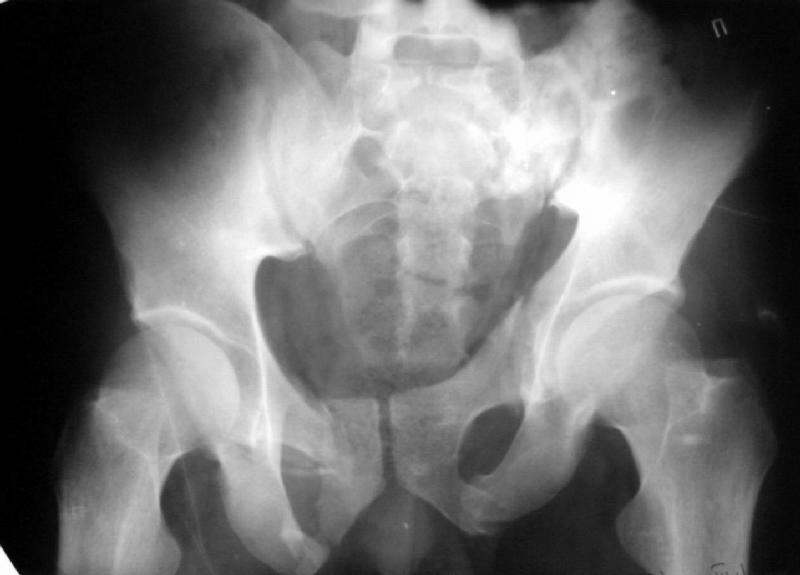

An example of our current approach to similar injuries - A 26 y.o. male admitted to us Aug 23, 2001 6 weeks after injury (compression by a wheel of a truck).

An external fixator was applied and gradual reduction was started - lateral traction to mobilize sacral fracture and then the hemipelvis was moved downward. Then lateral compression was performed. Yesterday iliosacral screws was inserted.

The last couple of images are skewed, they were made in OR and patient was not properly positioned.